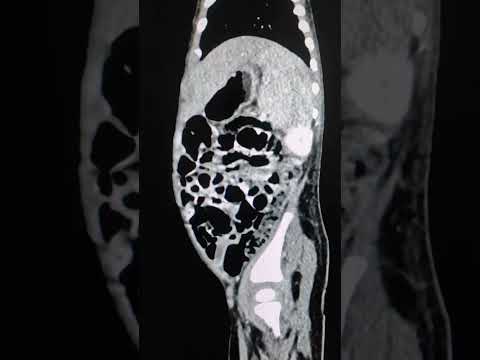

•     استئصال ورم الكلى ورم ولمز لطفل خديج يشغل معظم تجويف البطن

استئصال ورم الكلى ورم ولمز لطفل خديج يشغل معظم تجويف البطن